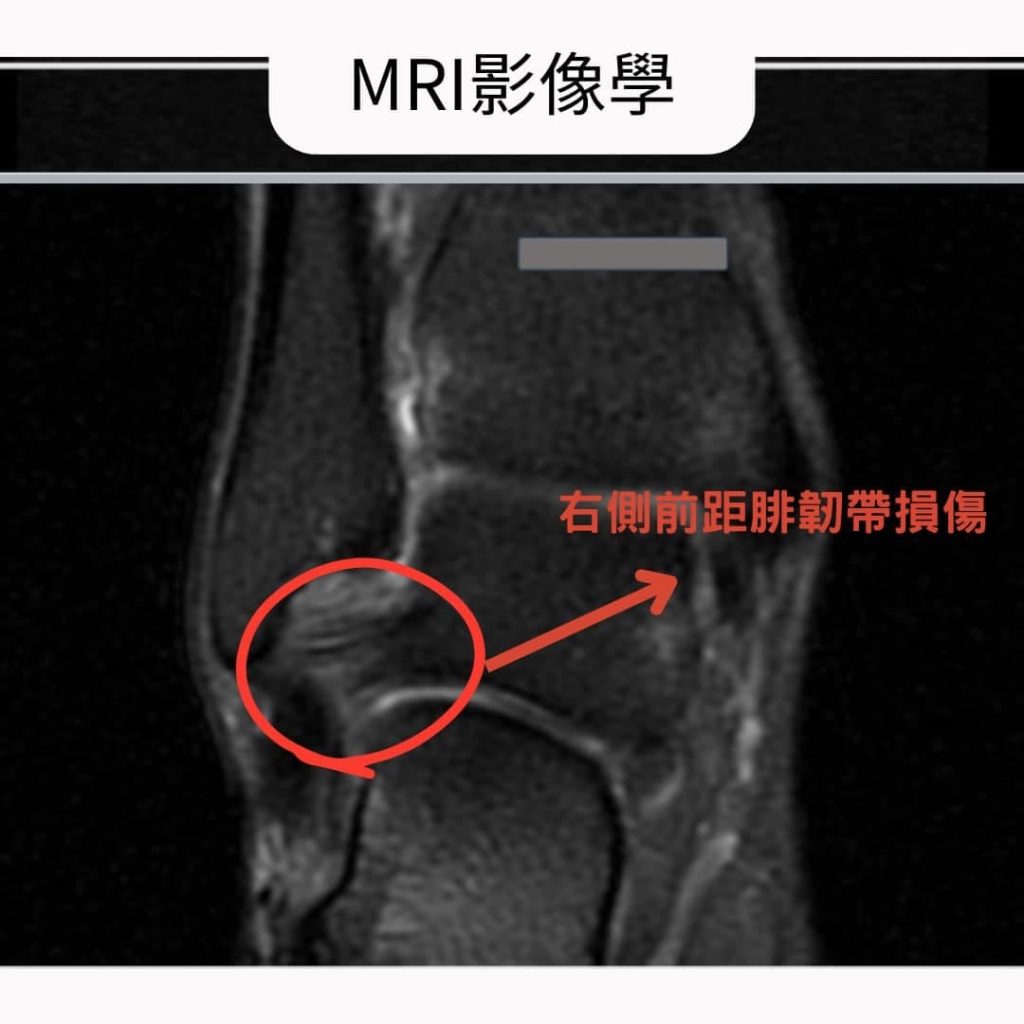

▪️影像檢查

超音波檢查也顯示蘇小姐右腳踝的外側韌帶有慢性扭傷的問題。而進一步的磁振造影檢查,也發現踝關節外側韌帶(圖示: 前距腓韌帶與跟腓韌帶)都有慢性損傷的問題。